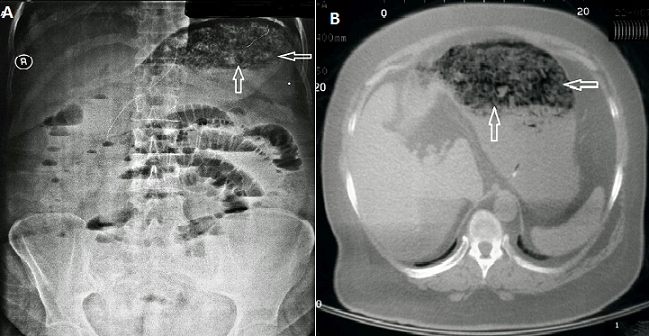

A rare image phytobezoar in stomach

42-year-old female patient came with complaints of 5 days abdominal pain, nausea, vomiting and constipation to our emergency service. No property was determined when chronic diseases of our patient, drugs used and history of surgery was questioned.It was learned that the purpose of slimming diet rich in fiber has been made for 10 days. Increase in bowel sounds on auscultation in the upper quadrant of the abdomen, while there was a decrease in the lower quadrant.The patient's vital signs were normal with normal laboratory values. Nasogastric tube was inserted in patients with vomiting, abdominal distension and constipation. There were air and liquid levels in the intestine in her direct abdominal radiographs, there was severely distended stomach and the gastric lumen had been filling with opacities (A). Intense soft tissue and isodense density which fills the lumen are available in the abdominal tomography, fluid and air leveling were observed in intestinal (B). Oral in take was stopped and intravenous hydration were started.The patient was discharged on the 5th day of hospitalization with a poor diet in fiber. In patients with out under lying chronic disease and a history of previous surgery, the patient can be given the chance of treatment with conservative method.